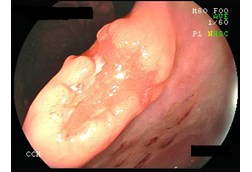

認識胃癌與最新檢查與治療